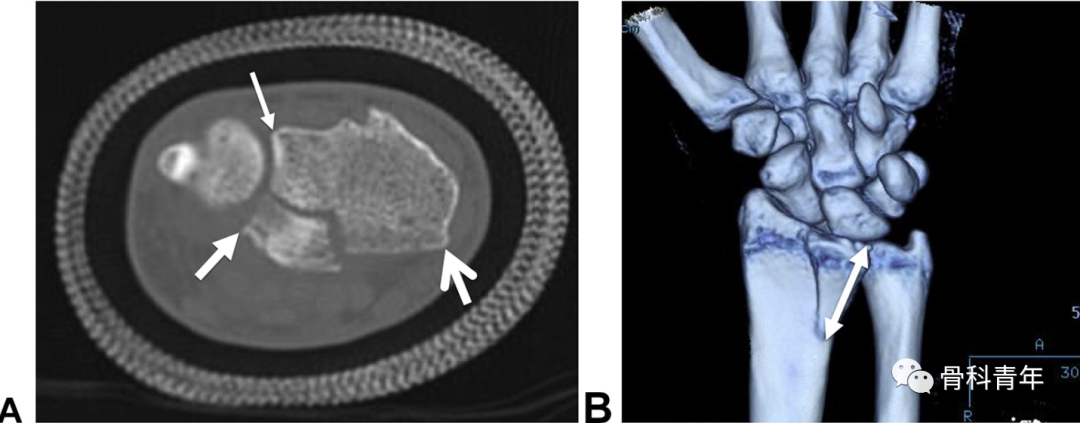

“四面体”型桡骨远端骨折概念:桡骨远端部分关节内骨折,骨折累及桡骨掌尺侧关节面及乙状切迹,横断位上呈三角形,骨折线延伸至桡骨干骺端。该骨折的特殊性体现在桡骨掌尺侧骨块的特殊性。一方面,掌尺侧骨块形成的月骨窝,作为抵抗腕骨向掌侧脱位的物理支撑,该结构的支撑作用消失导致腕关节掌侧脱位;第二,该骨块作为下尺桡关节桡骨关节面的组成部分,恢复其解剖位置是恢复下尺桡稳定性的前提。下图示病例1:典型“四面体”型桡骨远端骨折的影像表现。

在5年的病例中,研究中发现7例该类型骨折。在手术指征上,对上图病例1在内的3例无移位骨折病例,初次行保守治疗,但在随访过程中均出现骨折移位,而进行内固定手术;提示该类型骨折的不稳定性高,再移位风险高,手术指征强。在治疗上,2例采用传统桡侧腕屈肌入路钢板螺钉内固定,其中1例内固定失效骨块移位,采用掌尺侧入路,柱钢板特异性固定中柱翻修。出现内固定失效病例后,其后的5例病例均采用掌尺侧入路2.0mm或2.4mm钢板固定